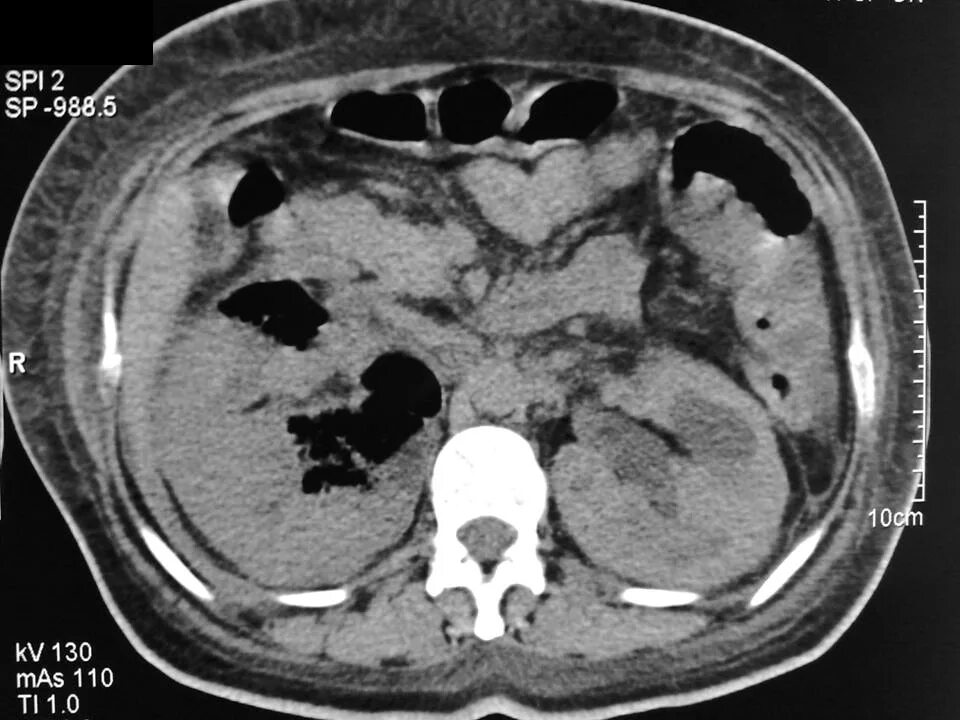

Пиелонефрит кт